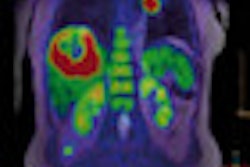

Swiss researchers have found that PET/CT scans with the radiopharmaceutical choline can change treatment plans for certain patients with recurrent prostate cancer. Study results showed that choline-PET/CT significantly affected therapy management.

"Choline-PET is a promising tool for detecting the return of prostate cancer with a high clinical influence," said study co-author Dr. Jan David Soyka, from the university's Institute of Nuclear Medicine, in a presentation at the RSNA 2011 meeting. "However, the limitation of this examination is that in patients where PSA levels are low -- below 2 ng/mL -- we find many patients do not have positive findings. So, the question arose: Is there any subgroup of patients who may have an increased benefit from this examination?"